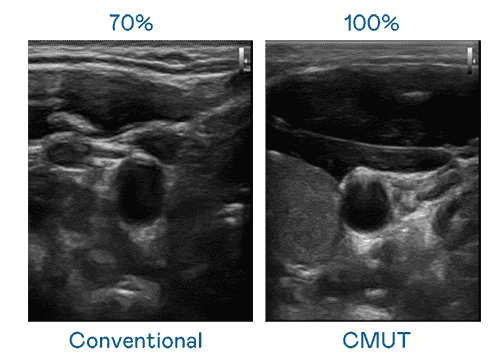

CMUT 技术是一种用电容式微机电元件来产生超音波讯号的技术。。。。与传统 PZT 压电式技术相比,,,CMUT 频宽增加 30%,,,,更宽频的超音波讯号让影像解析度大幅提升,,是实现高影像品质医疗超音波扫描、、、促进精准医疗发展的关键技术。。。

大频宽带来超清晰影像

超音波影像的解析度高低,,,首先取决于探头能发出的讯号频宽。。。。www.z6.com CMUT 可提供高清晰的超音波讯号,,,提供高频宽、、高灵敏度、、、影像纹理细节更高的超音波影像,,,协助医护人员缩短影像判读时间及利用精准的医疗影像进行诊断。。。